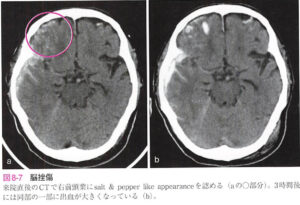

| 脳挫傷 | 脳実質損傷のことで、実質組織の破壊と微小血管の破綻により、脳浮腫と小出血が混在する。![]() |

脳挫傷・外傷性脳内血腫

| 病態 | 脳実質損傷のこと。脳挫傷による小出血が癒合し、脳内血腫に進展して形成されることが多い。 ※出血部位が前頭葉や側頭葉にあることが脳出血との鑑別点に有用 |

| 症状 | |

| 検査 | 頭部CT:時間経過とともに冠状断像でごま塩状の変化が見られることがある![]() |